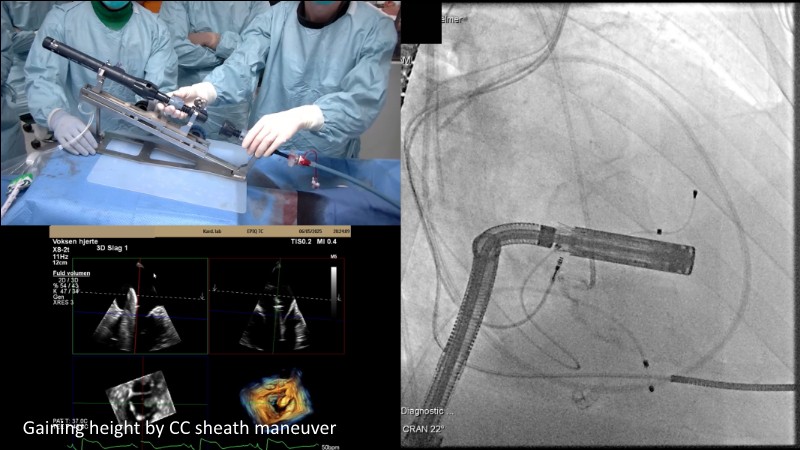

This EuroPCR 2025 session highlights the evolving role of transcatheter mitral valve replacement, focusing on the clinical potential of mitral regurgitation elimination. Get an overview of the current status of the Intrepid TMVR programme, learn about the transition to the 29Fr transfemoral system, and explore how patient screening—especially in the presence of mitral annular calcification—impacts procedural planning. Real-world case reviews from the APOLLO-EU trial offer practical insights into how this next-generation system is being applied in Europe today.